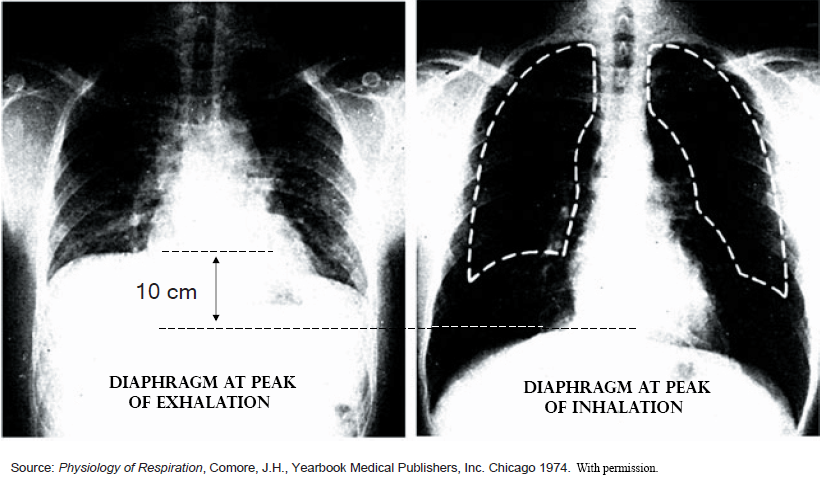

In this single page article, Stephen Elliott describes the physiology of the injury known as a “pneumothorax”, a hole in the wall of the chest and thoracic cavity.